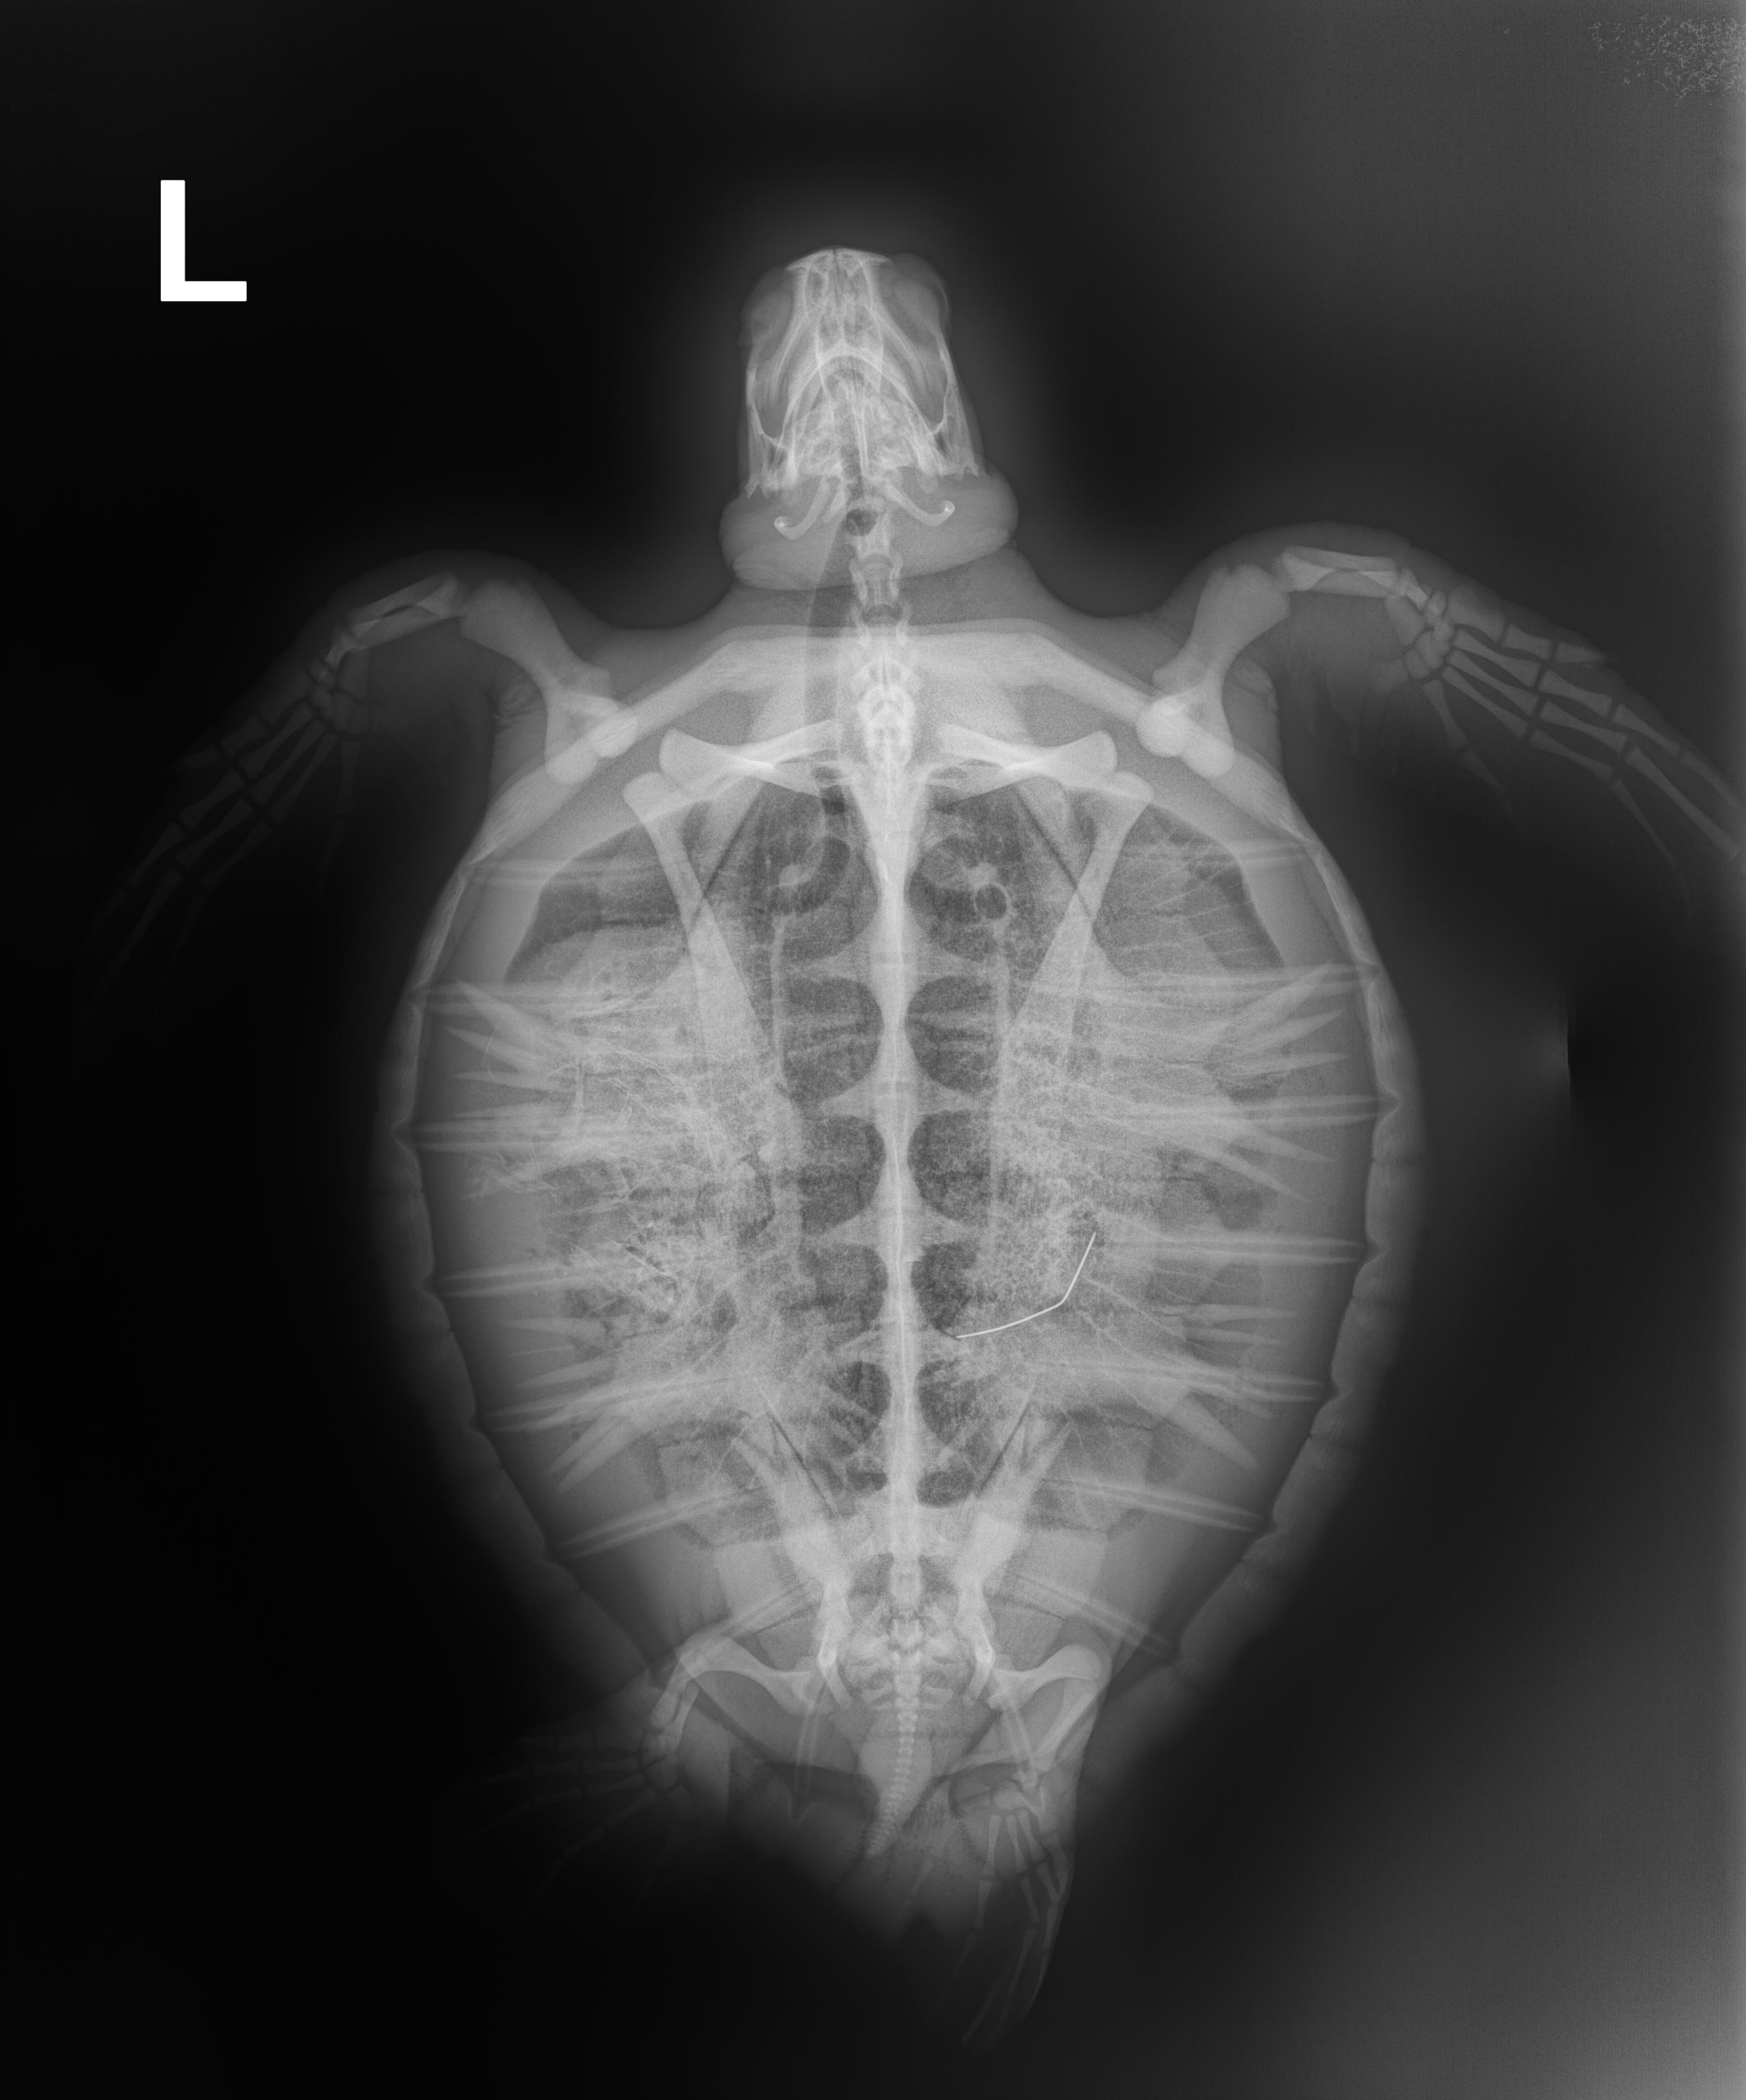

4.9 lbs. non -FP juvenile green

Patient Injuries

Entangled around the neck with braided fishing line

In-house PCV = 26 %, TP = 3.8 g/dl, glucose = 179. Started on Ceftaz, Vitamin B, Normosol and Meloxicam.